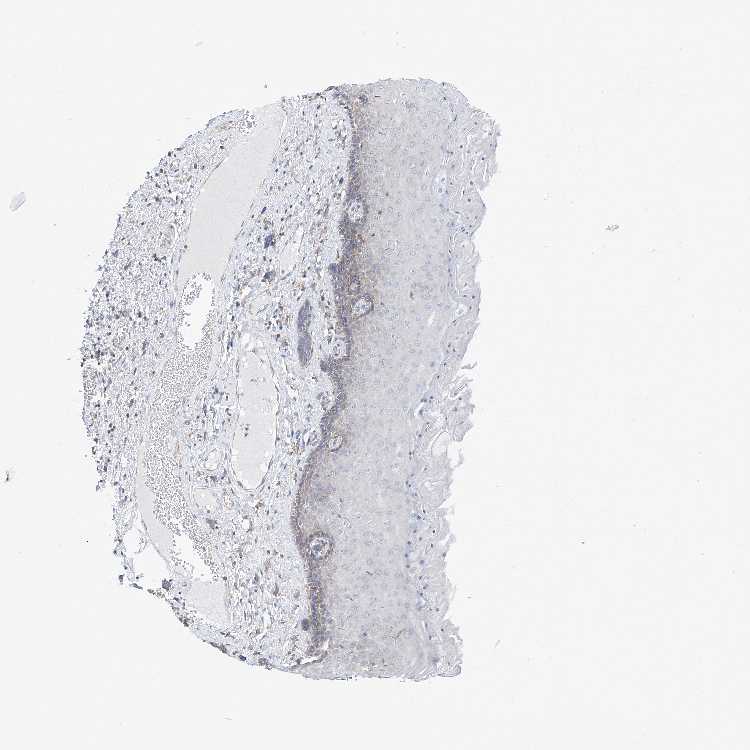

SKIN 2 - Antibody stainingi

Antibody staining in the annotated cell types in the current human tissue is reported as not detected, low, medium, or high, based on conventional immunohistochemistry profiling in selected tissues. This score is based on the combination of the staining intensity and fraction of stained cells.

Each image is clickable and will lead to virtual microscopy that enables deeper exploration of all samples and also displays staining intensity scores, fraction scores and subcellular localization as well as patient and tissue information for each sample.

Antibody HPA003348

Epidermal cells Low